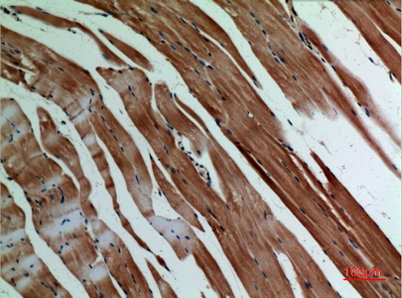

Product name: α-SMA rabbit pAb

Alternative Names: ACTA1; ACTA; Actin, alpha skeletal muscle; Alpha-actin-1; ACTA2; ACTSA; ACTVS; GIG46; Actin, aortic smooth muscle; Alpha-actin-2; Cell growth-inhibiting gene 46 protein; ACTC1; ACTC; Actin, alpha cardiac muscle 1; Alpha-cardiac actinACTA1; ACTA; Actin, alpha skeletal muscle; Alpha-actin-1; ACTA2; ACTSA; ACTVS; GIG46; Actin, aortic smooth muscle; Alpha-actin-2; Cell growth-inhibiting gene 46 protein; ACTC1; ACTC; Actin, alpha cardiac muscle 1; Alpha-cardiac actin

Dilutions: Western Blot: 1/500 - 1/2000. IHC-p: 1:100-300 ELISA: 1/20000. Not yet tested in other applications.

Immunogen: Synthesized peptide derived from the C-terminal region of human α-SMA.